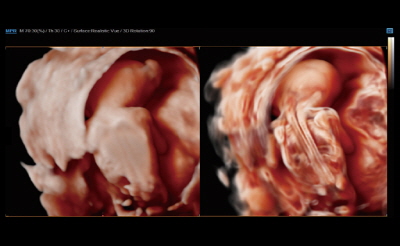

입체 초음파 영상 장비 (삼성 HS50)

초음파 영상에 음영효과를 입혀 입체감 있게 보여주는 기술이 적용된 장비입니다. 태아의 발달과 이상 유무를 자세히 확인하실 수 있습니다.

태아의 초음파 영상은 '세이베베' 서비스를 통해 핸드폰과 PC로 확인하실 수 있습니다.